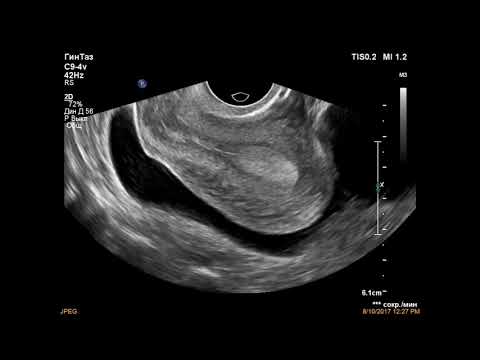

Фото:Резекция яичника

Фото:Резекция левого яичника

Фото:Резекции яичников и беременность